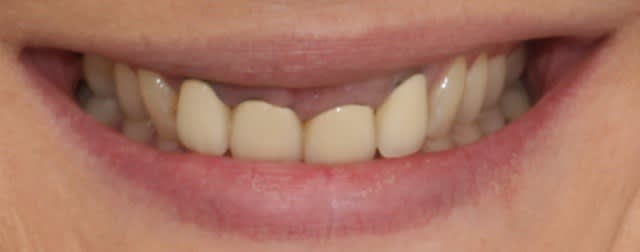

Elle a un sourire gingival.

Peut être des dents qui ne donnent pas l'impression d'avoir été taillées dans une défense d'éléphant ?

voilà, elle veut des dents.

J'ai éclaté de rire, quel sourire dégueulasse :))))

Par contre évaluer ce qu'il va rester de l'os et des tissus mous après élongation coronaire (11 et 21 suffiront) pour garantir de conserver une papille (ou plutôt 3 papilles) digne de ce nom et bien plus complexe:

Solution 1: Ingression ortho de 21 et 11 (voir le récent post de seespan et son doc réponse sur les gummy smille)

Solution 2: Elongation coronaire 11 et 21 , réharmonisation de la ligne gingivale, vu que l'ortho t'as semblé ésotérique, je suppose que la soluce 2 a été choisi, donc on attend le compte rendu opératoire ;-).